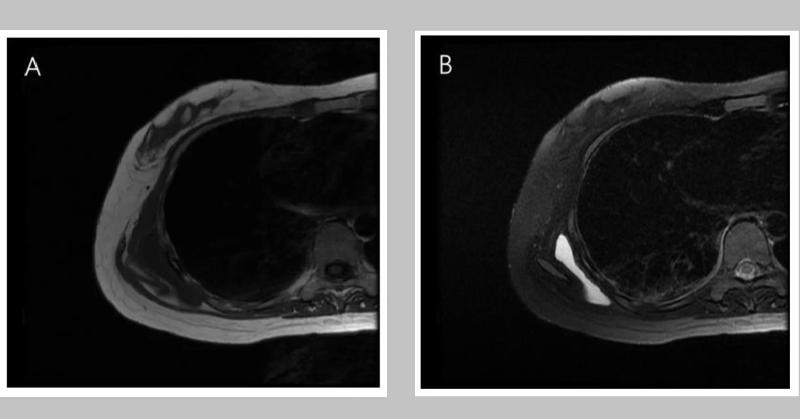

Painful Shoulder Lump in Woman with SLE: What Could It Be?

A 34-year-old woman with a history of systematic lupus erythematosus (SLE) presented with a palpable lump and pain in her right shoulder. MRI revealed scapulothoracic bursitis. Histopathological examination confirmed the diagnosis of bursitis with cystic degeneration and recurrent bursitis. Her shoulder movement remained unrestricted, and she did n